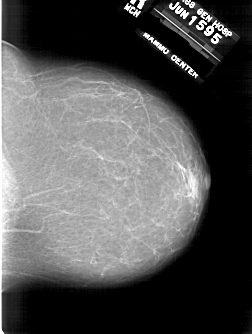

Со старением железистая ткань постепенно исчезает: прозрачность жировой ткани становится преобладающей с несколькими каркасами, связанными с опорными волокнистыми структурами.

Жирная (не плотная) грудь

Умеренно плотная грудь

Плотная грудь

Маммограммы представляют собой изображения структур, проецируемых на плоскость: плотная грудная маммограмма, следовательно, состоит из многих других структур, которые необходимо проанализировать, чем более жирная, пустая грудь. По этой причине диагностировать рак молочной железы труднее для моложе, чем для пожилых женщин.

Нажмите на миниатюрные картинки, чтобы получить увеличенный размер.